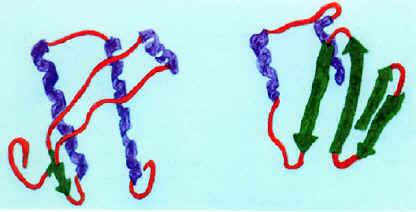

A lâmina A é sintetizada por uma molécula precursora, denominada prelamina A, em quatro etapas pós-tradução. Todas as prelaminas apresentam um domínio globular na sua extremidade C-terminal e outro na N-terminal. O terminal carboxílico contém um motivo característico CAAX (C é cisteína, A é um aminoácido alifático e X é o aminoácido terminal) que é modificado por farnesilação, ou seja, uma feniltransferase adiciona um grupo farnesil (isoprenóide de 15 carbonos) em proteínas que possuem a cisteína no terminal carboxilo.

Posteriormente ocorre uma libertação endoproteolítica dos três últimos aminoácidos da proteína, seguida de metilação do terminal carboxílico farnesil-cisteína por uma metiltransferase. Por último ocorre a libertação endoproteolítica dos últimos quinze aminoácidos havendo libertação da lâmina A. Este esquema de processamento é crucial para a adesão da lâmina A ao invólucro nuclear.

A mutação mais frequente no gene LMNA, em casos de progeria, é originada pela substituição de um nucleótido na posição 1824, de citosina para timina, esta mutação não origina troca de aminoácido, mas ativa um sítio de splicing críptico (áreas alternativas ao splicing que competem com as áreas normais) que provoca a deleção de 50 aminoácidos do terminal carboxílico (Figura 1).

Na progeria o sítio de reconhecimento da enzima que requer a clivagem da prelamina A a lâmina A está mutado, não ocorrendo clivagem do grupo farnesil, formando assim uma proteína anormal denominada de progerina, uma forma truncada da prelamina A. A progerina é tóxica para a célula, acumula-se nas células causando defeitos moleculares progressivos, incluindo alterações do formato nuclear, desorganização da cromatina, danos no DNA e atraso na proliferação celular (Figura 2).